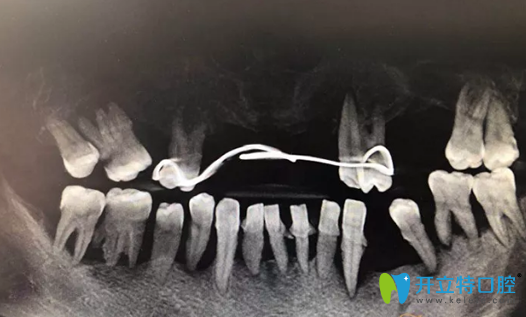

種植修復前CBCT影像:

重慶牙博士種植修復前CBCT影像

種植牙術(shù)后即刻照片及修復后CBCT影像:

重慶牙博士徐孟輝種植牙術(shù)后即刻照片及修復后CBCT影像